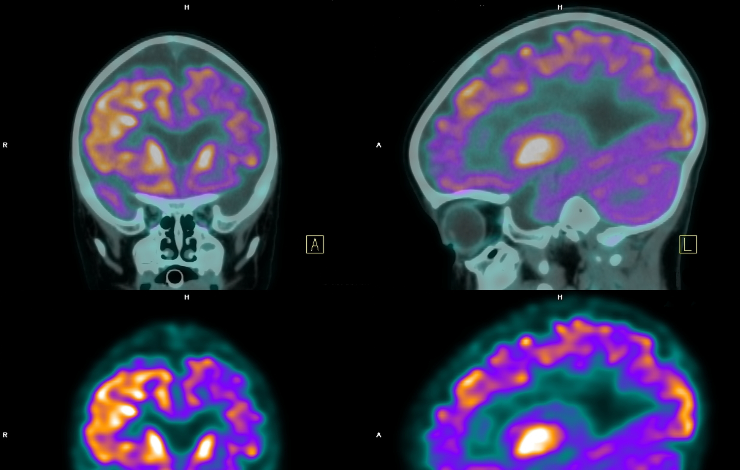

​Une collaboration de chercheur impliquant le CEA-Joliot a participé au développement de PET KinetiX : un logiciel capable de générer des images 3D du corps humain pour suivre la circulation des biomarqueurs de certains cancers. Utilisé pour l’imagerie TEP, il pourrait permettre aux médecins d’obtenir de nouvelles données biologiques sur leurs patients. Après de premiers essais prometteurs sur un simulateur numérique, le logiciel est désormais testé dans plusieurs centres hospitalo-universitaires.

Première mise à l'épreuve réussie sur un simulateur numérique

Appelé « PET KinetiX », le logiciel est capable de modéliser très rapidement les paramètres biologiques pour générer des images 3D des flux d'échanges intracellulaires du radiomarqueur en fonction du temps. Compatible avec tous les appareils TEP, il a été testé sur les données fournies par un simulateur haute résolution de l'anatomie humaine qui a reproduit plus de 400 TEP dynamiques sur des organes et parties du corps différents.

PET KinetiX a ainsi pu démontrer qu'il était capable de produire des TEP dynamique avec un niveau de détail identique à celui d'images TEP cliniques standards et même meilleur dans le cas de données provenant d'appareils récents à champ de vision étendu. Le logiciel ouvre ainsi la voie à une utilisation de la TEP dynamique en clinique qui fournira aux médecins de nouvelles données biologiques importantes pour le diagnostic et le suivi des patients. Développé avec le laboratoire de mathématiques d'Orsay, il est actuellement testé académiquement dans plusieurs centres hospitalo-universitaires en Europe et en Amérique.